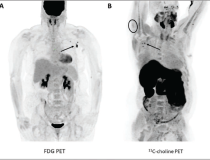

This photo gallery shows the variety of radiological presentations of COVID-19 (SARS-CoV-2) in medical imaging, including computed tomography (CT), radiograph X-rays, ultrasound, echocardiograms and magnetic resonance imaging (MRI). The radiology images show examples of typical COVID pneumonia in the lungs and the numerous complications the virus causes in the body in multiple organs, including the brain, kidneys, heart, abdomen and vascular system.